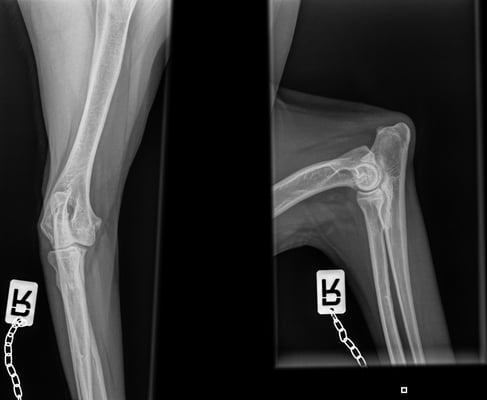

Lahmheitsuntersuchungen

Untersuchung und Abklärung von Lahmheiten

digitale Röntgenuntersuchung in der Praxis

Erstellen von HD und ED Röntgen für die offizielle Auswertung